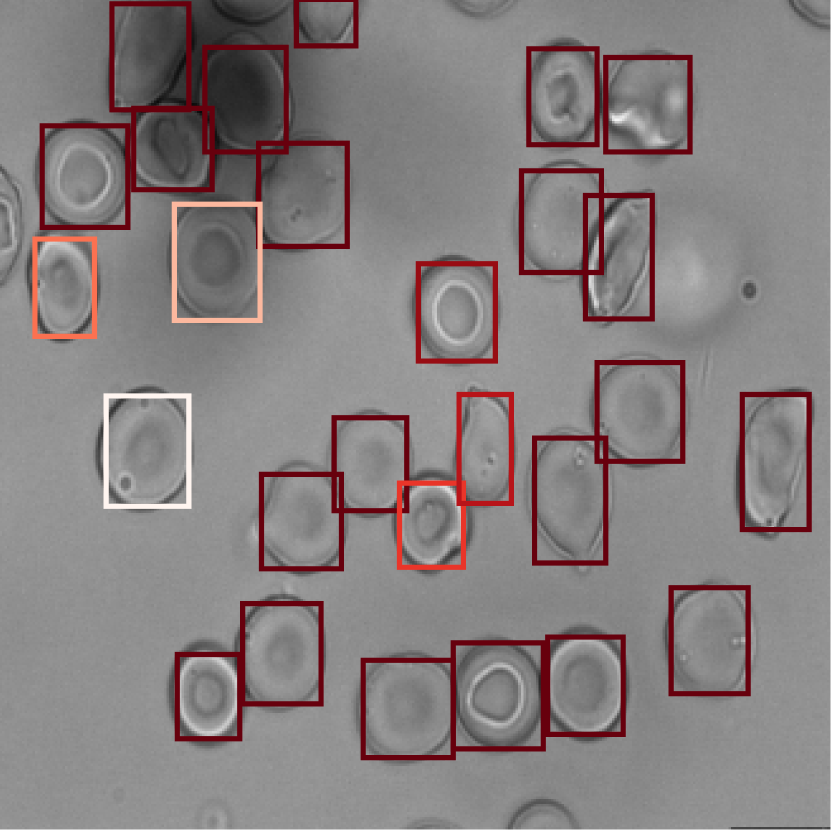

3.2 Explainability

Our method’s anomaly scoring mechanism is interpretable at the instance level. In Fig. 3, for each class, we visualized a sample image, in which anomaly and attention scores are depicted by the color of the cell’s bounding box. The anomaly mechanism can distinguish class-related cells better than the attention mechanism, which is particularly striking for the SCD case, where irregular elliptoid cells are missed by the attention mechanism (Fig. 3). In Fig. 4 we show the distribution of scores assigned to cells in the test data. The frequency of both anomaly and attention scores are focused around zero, which is compatible with a majority of healthy cells (see also Fig. 4). On the other hand, for HHA, a small distribution of high scores notifies the anomalous cells. These cells show HHA properties.

Figure 3: Interpretation of bag classification at the instance level based on anomaly (top) and attention (bottom) scores. Compared with attention mechanism, disorder-relevant cells are more accurately scored by the anomaly mechanism.